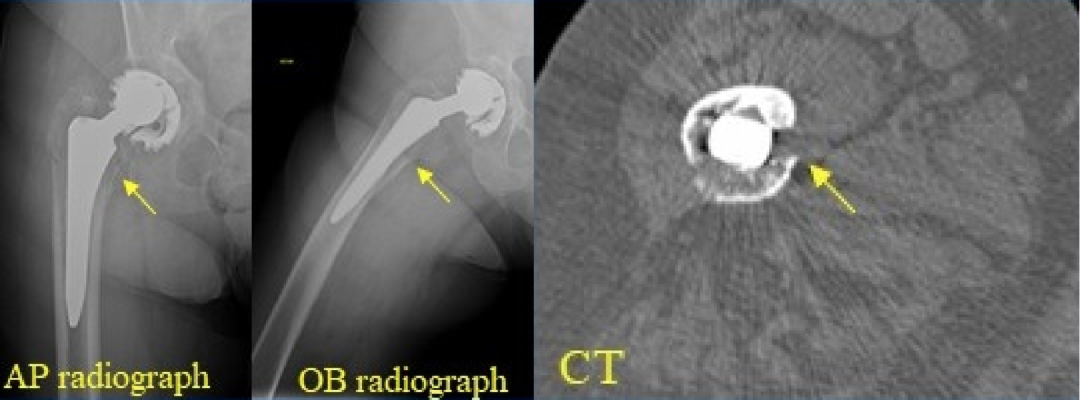

5. Metal-on-metal(MOM)disease:

假性滑囊,是金属对金属髋关节置换的组织反应;表现为髋关节假体周围的滑囊。最常见的部位是:髋臼上缘、大粗隆和小粗隆。

人工髋关节置换术。假体周围囊性肿块(箭头)